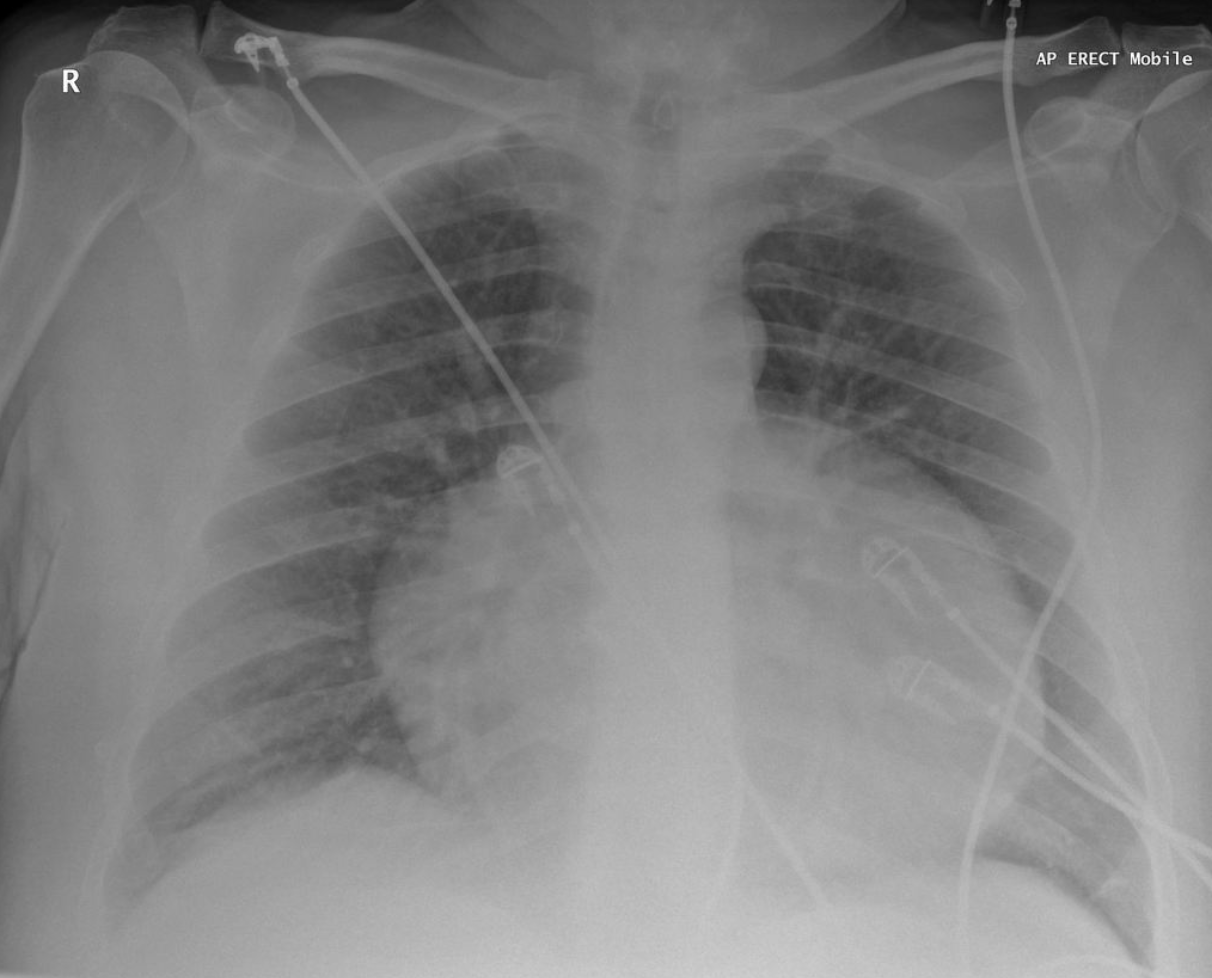

Atrial lead fracture (right by box), right pleural effusion,